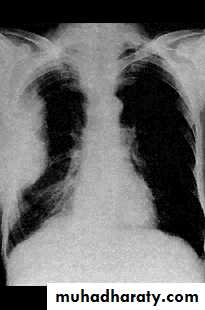

Radiology

Chest X-ray: typically small lung volumes with reticulonodular shadowing

Abnormal chest X-ray at presentation with lower zone bi-basal reticular and reticulonodular opacities. 'honeycomb' appearance in advanced disease.